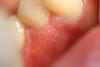

Marina_A Опубликовано 12 мая, 2013 Поделиться Опубликовано 12 мая, 2013 Коллеги, что это может быть?Воспалилось после ретракции десны. нитку при этом ничем не смачивала, аллергии быть не должно. со слов пациента с ним такое бывало во время простуды, но пузырьки были в единственном числе и проходили сами. Сейчас же все обостряется, болит, зудит.Что это? Может Герпес? Ссылка на комментарий

Magdalena Опубликовано 12 мая, 2013 Поделиться Опубликовано 12 мая, 2013 На герпетический стоматит действительно похоже. Ссылка на комментарий

Мармышка Опубликовано 12 мая, 2013 Поделиться Опубликовано 12 мая, 2013 а мне кажется, что при герпетическом стоматите более гиперемированная и отёчная слизистая вокруг... могу, конечно же, ошибаться Ссылка на комментарий

kama2005 Опубликовано 12 мая, 2013 Поделиться Опубликовано 12 мая, 2013 а мне кажется, что при герпетическом стоматите более гиперемированная и отёчная слизистая вокруг... могу, конечно же, ошибаться Ну на пузырчатку тож не очень похоже... Думаю, что и не ветрянка...Я тож за герпес) Хотя локализация и смазанность симптоматики тоже смущают) Ссылка на комментарий

Marina_A Опубликовано 13 мая, 2013 Автор Поделиться Опубликовано 13 мая, 2013 BORA, нет, перекисью ничего не обрабатывала. Пузырьки лопнули, образовав кучу маленьких эрозий.пока лечим герпес. динамика положительная Ссылка на комментарий